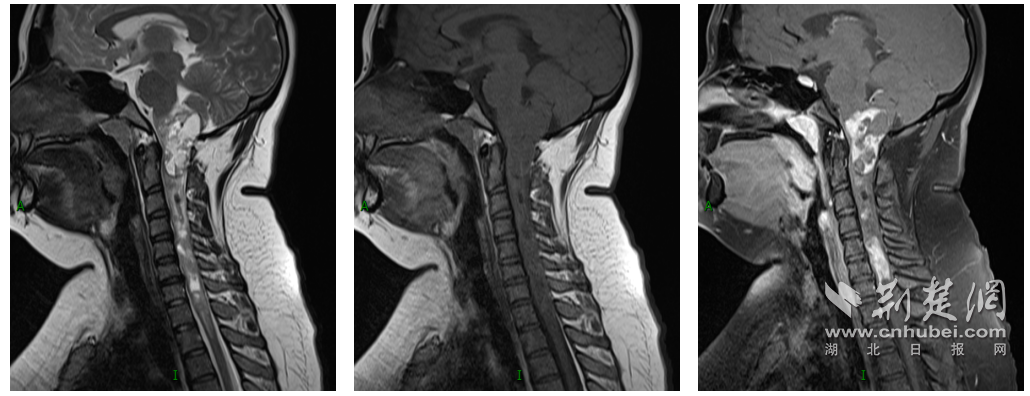

荆楚网(湖北日报)讯(通讯员:熊婉婷 张丽华 陈有为 摄)21岁女孩小腿无力,行走困难。结果发现,一个危险的肿瘤已经占据了他大脑的“座位”,并已扩散到颈椎和胸椎脊髓。手术的风险非常高。稍有不慎,就会导致四肢瘫痪,甚至危及生命。近日,华中科技大学同济医学院附属协和医院(以下简称“协和医院”)神经外科专家团队勇敢地进入手术限制区域,成功实施了难度较大的颈胸段脊髓长节段肿瘤切除术,消除了这枚位于其生命中心的“定时炸弹”。患者术后恢复顺利,已于12月13日安全出院。一个月前,小婷女士(化名)突然她出现了右腿无力、行走困难等症状,严重影响了她的日常生活。在当地医院接受检查后,他被诊断出患有“颈脊髓占位性病变”。由于肿瘤位于脑干、脊髓和主要血管结构附近的独特位置,手术极其困难。小婷去过多家医院寻求治疗,但都没有效果。经过多方会诊,小婷于11月23日在家人的陪同下来到协和医院神经外科就诊。接到诊断后,神经外科周迎春教授对小婷女士进行了全面检查,发现她的肿瘤已从延髓向脊髓、颈部和胸部生长。延髓位于脑干的底部。它是控制呼吸和心跳的“生命中枢”。多条神经和血管肿瘤生长较大、连续(脑干脊髓长度可达15cm,延髓内病灶大小约5cm×4cm×2cm),严重压迫脑干及周围脊髓组织。最薄的部分薄如纸。在解剖学上重要的部位进行手术就像“在刀尖上跳舞”。即使是最轻微的疏忽,也可能导致严重的后果,例如四肢瘫痪、呼吸停止、心脏骤停等。然而,如果不及时进行手术,随着肿瘤不断生长并对颈脊髓造成压力,随时可能危及生命。为了根除肿瘤,并为最大程度地保护神经病学功能,周迎春教授组织了多次关于癌症前期的深刻辩论,并提出了精确、个性化和整体治疗的计划。奥亭。皮肤的主要潜力包括血液循环障碍、脑血管入侵、生命器官灌注、肌肉呼吸暂停和神经功能障碍等。后部并发症如肺部感染、胃肠道出血和内部环境变化。照片:术前磁力共振将损伤部位延伸至球部,以延长椎体的底漆。照片:手术团队进行显微手术。照片:四个孤立病灶的完整切除:(从左到右)病灶和延髓:椎体水平 C2、C4、C5-7 和 T1。 11月26日,周迎春教授、朱文德副教授带领团队,在麻醉科、手术室、神经外科等科室的配合下,为科巴先生完成了这场艰难的手术。nts。手术过程中,专家们在神经电生理控制下使用显微镜扩大手术视野,平静地进行手术,耐心细致地解剖肿瘤与周围血管、神经的粘连。经过近五个小时的显微手术,病变组织终于被彻底切除。凭借主刀医生丰富的手术经验和默契,在团队的配合下,小婷成功克服了手术的困难。脑干和脊髓的功能得到最大限度的维持,即使术后也没有出现肌麻痹、烧心、四肢瘫痪的情况。术后病理检查显示,病灶为室管膜瘤(WHO 2级),属低度恶性肿瘤。照片:术后MRI显示病灶已完全切除,对正常延髓的压力最小。近距离车下在医疗队的帮助下,小婷逐渐康复。术后6小时,小婷恢复自主呼吸,摘除呼吸机(维持鼻插管)。术后第二天气管插管成功拔除。确认吞咽和咳嗽反射正常后,患者开始进食流质食物。右腿无力等症状明显改善。他安装了支架,大约一周内他就能够下床并开始康复锻炼。 12月13日,小婷顺利出院。周迎春教授指出,影响颈、胸脊髓的大面积室管膜瘤相对罕见,如果任其发展,后果是可怕的。目前,手术切除是最有效的治疗方法,但手术有风险,需要外科医生和团队之间非常密切的合作。它需要能量。他回忆说,你脊髓的mor病变一般比较隐蔽。当出现四肢麻木、四肢无力、步态不稳等症状时,要及时就医,尽快发现可能的“定时炸弹”。据了解,武汉协和医院神经外科在国内率先设立脊柱脊髓亚专科,拥有成熟的亚专科培训体系和优秀的人力资源。经过多年的发展,我院亚专科专家团队在复杂脊髓病变的显微外科治疗方面积累了丰富的经验,包括退行性病变(颈椎病、腰椎病、椎管狭窄症)、肿瘤病变(神经鞘瘤、室管膜瘤、脑膜瘤)、发育性/创伤性/病理性畸形(小脑)等,年均手术量近千例程序。扁桃体下疝畸形、颅底凹陷/寰枢椎脱位、脊髓栓系等)照片:周迎春教授团队确认患者康复情况 上一篇:农村党支部书记变身“卖家”,售出数千吨柑橘